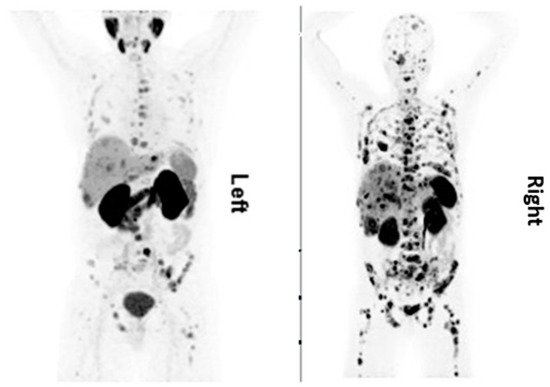

3.5. Pharmacogenomics-Based Markers

The current Delphic consensus is that an accurate circulating biomarker that captures the biological activity of a NET and predicts its clinical behavior would provide an optimal method for the early detection of disease progression [36]. The NETest is a 51 multigene assay based on PCR analysis of specific NET circulating transcripts, and its results are depicted in the form of a score. It portrays the circulating NET fingerprints and exhibits a higher sensitivity and specificity (98 and 97%, respectively) than secretory markers for identifying neoplasia [37,38]. The assay is standardized and highly reproducible (inter- and intra-assay coefficient of variation <2%) and is postulated to be independent of tumor heterogeneity. Gene expression is captured in a 0–8 score derived from 4 different prediction algorithms that is mathematically scaled to disease activity (0–100%) by interpolating the expression of ‘omic’ transcripts that define specific biological components (hallmarks) of neoplasia. The clinical utility benefit has been documented in several independent clinical studies using diverse therapeutic strategies. In addition, the NETest has been demonstrated as an effective (85–90% accuracy) surrogate biomarker for tumor progression measured with conventional imaging with CT/MRI. A short PFS is significantly correlated (>95%) with increased blood biomarker levels > 40 (on a scale of 0–100). Similarly, RECIST progression of patients on somatostatin receptor binding analogs is also significantly associated (>90%) with increase in score. However, stabilization or response is associated with no change or reduction in scores (NETest levels ≤ 40). These alterations (progression NETest score > 40; disease stability ≤ 40) likely reflect the biological impact of treatment [39]. In neuroendocrine neoplasms of gastrointestinal tract, higher expression levels in tumor relative to non-tumor tissue of > tenfold were found for CgA, 2—tenfold higher mRNA levels were found for CD56, β-catenin, PDX1, CK20, and P53 and 1—twofold higher mRNA levels were found in CD45 tumor tissue compared with the non-tumor tissue [40]. A similar approach of using ‘omics’-based prognostication can also be used in prostate cancers, wherein the entire fulcrum of management is based on the biochemical value of PSA. Dysregulation of miRNAs (miRs) has been reported in prostate malignancy from early- to advanced stage and castration resistant disease progression [41]. Among differentially expressed miRNAs, most interestingly, the expression of miR-301 was upregulated in early-stage and CRPC progression, and this high expression of miR-301 was consistent in both serum and tumor tissue in prostate cancer patients compared to patients with benign prostate hyperplasia. In addition, miRNA regulatory genes during stage-specific prostate cancer progression suggest the involvement of p53, EGFR-PI3K-Akt, IGF, interleukins, TGFB, VEGF, JAK/STAT, WNT signaling and their effectors as the most critical genes in prostate cancer via upregulation of growth factor receptors, specifically EGFR, or through PTEN inactivation. An example of a patient with neuroendocrine differentiated prostate cancer is shown in Figure 2.